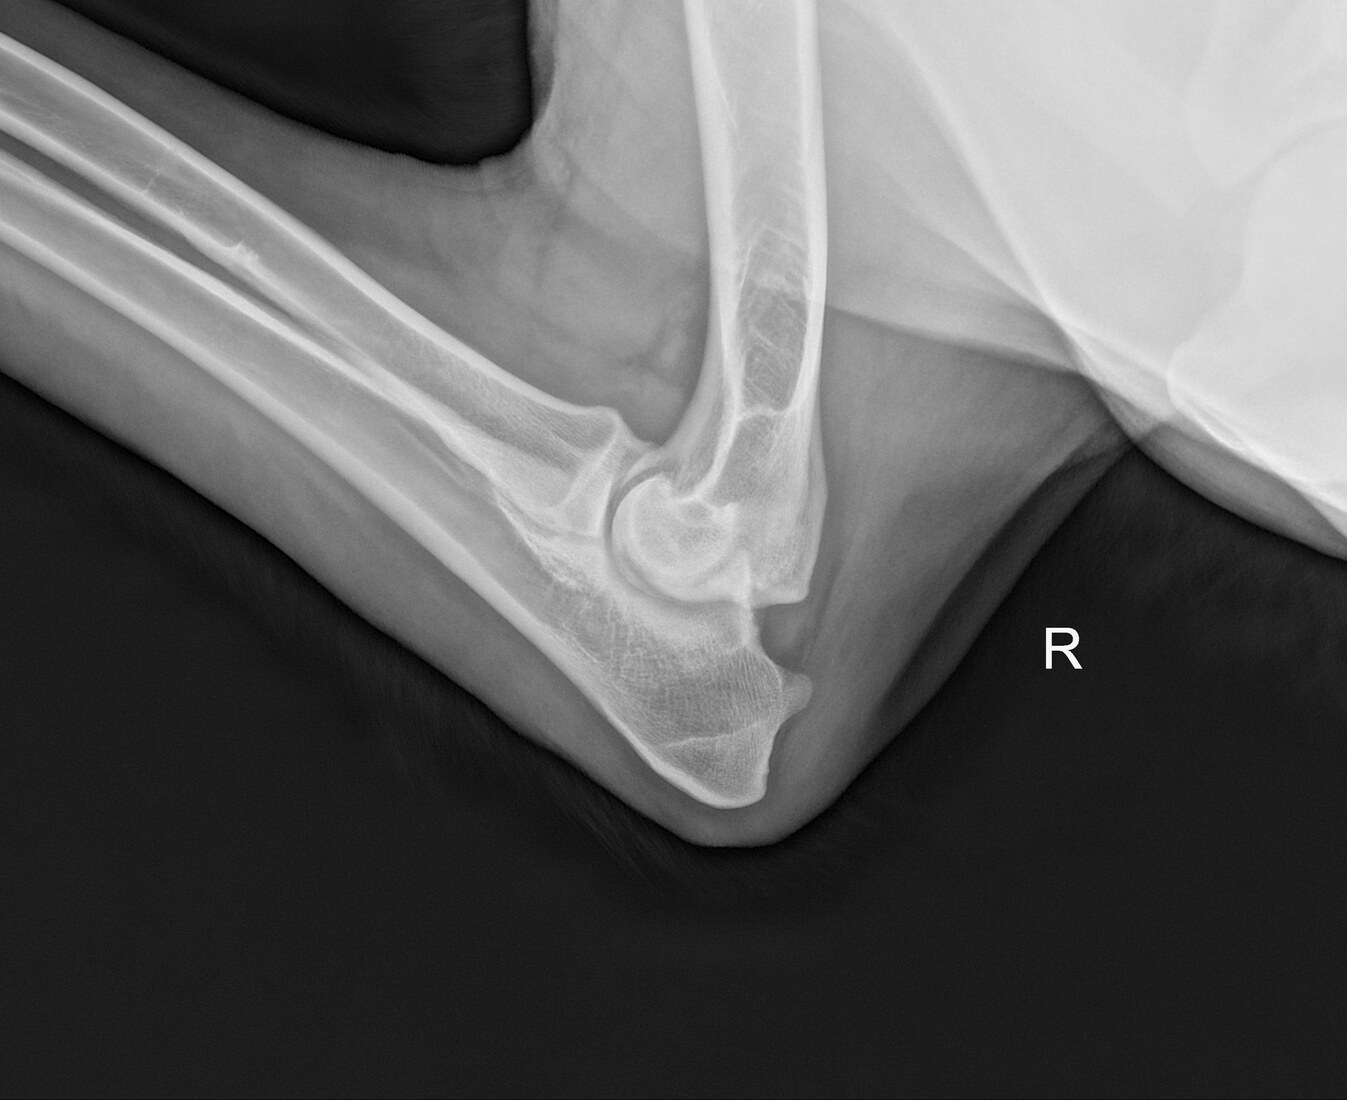

Bentley